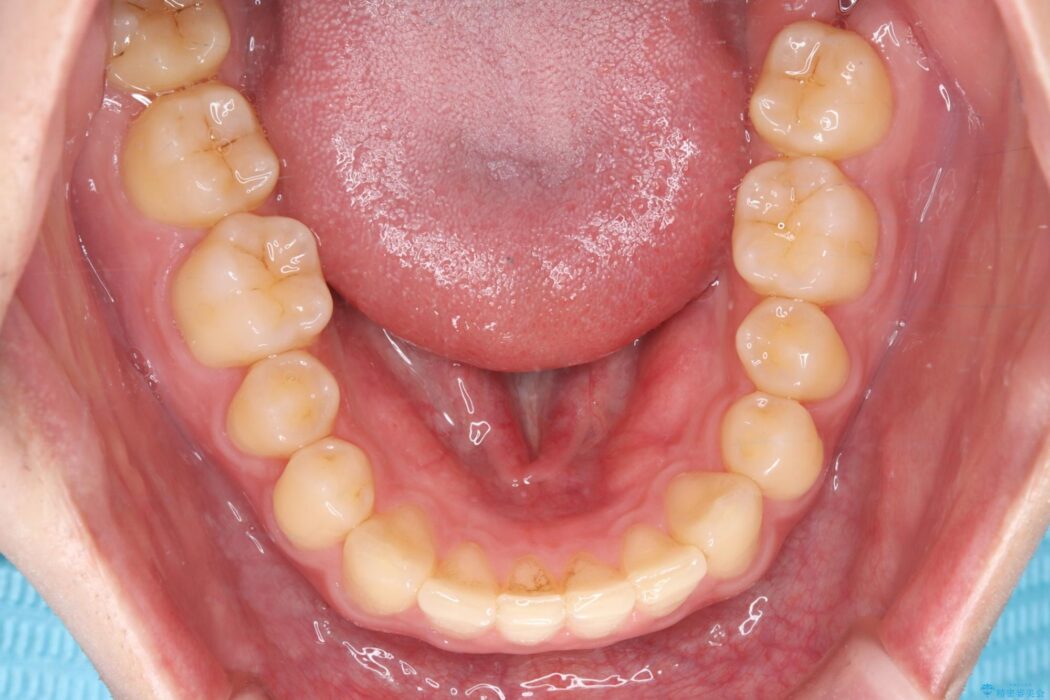

上顎中切歯間の隙間の他にもフロスが抵抗なく入るスペースが上顎は数か所ありました。スペースを閉じ下顎の歯列弓との調和をとるためIPRを行いました。

下顎の舌側傾斜気味の前歯も唇側へ歯軸傾斜させています。